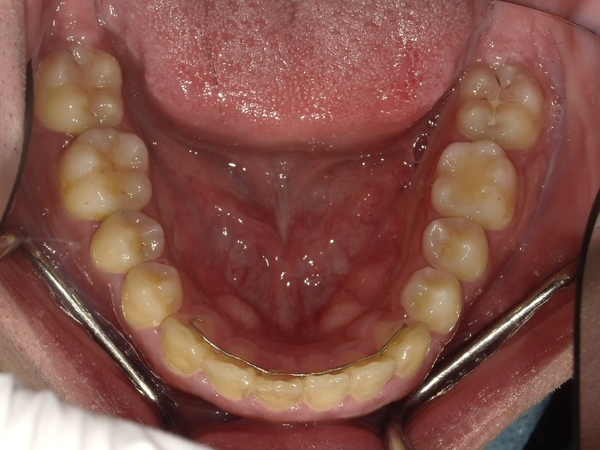

すきっぱ(空隙歯列)CASE7 2023.08.28 20代男性☆Before→After☆〇ご相談内容:前歯真ん中の隙間があいている〇矯正の種類:マウスピース型矯正「インビザラインGO」〇治療期間:19週間〇治療費用:44万円(税込) < すきっぱ(空隙歯列)CASE8すきっぱ(空隙歯列)CASE6 > ブログ記事一覧をみる